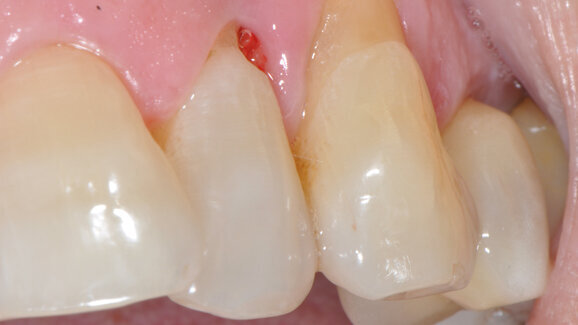

Dopo avere eseguito la diagnosi, si è informato il paziente della condizione patologica e della necessità trattare nella stessa seduta i siti più gravi (Tab. 1) per poi pianificare a distanza di 3 settimane un’adeguata seduta di OSFMD. È stato fatto firmare il consenso informato e si è proceduto all’applicazione di un gel al 25% di metronidazolo (MTN) fornito dal CNR di Pisa. La procedura prevedeva una blanda decontaminazione sopragengivale con strumenti piezoelettrici (Air Flow Master Piezon, EMS) (Fig. 1), l’applicazione tramite siringa e pennellino dell’agente reticolante a livello marginale (Fig. 2) e intrasulculare (Fig. 3), il posizionamento del gel di MTN tramite apposita siringa e ago smusso da 0.9 mm nel fondo della tasca (Fig. 4) e, infine, una nuova applicazione di reticolante (Fig. 5). I pazienti sono stati dimessi con l’indicazione di non sciacquare, bere o mangiare per l’ora successiva e di non usare colluttori antisettici fino all’appuntamento di rivalutazione e terapia OSFMD. Le Figure 6-18 mostrano nel dettaglio uno dei casi clinici trattati e le Figure da 19-29 mostrano le immagini cliniche al baseline (T0) e a 3 settimane dall’applicazione di MTN (T1) degli altri casi trattati.

Come mostra la Tabella 2, i risultati ottenuti con una monosomministrazione di MTN in siti acuti, senza nessun altro trattamento aggiuntivo, hanno portato alla normalizzazione dell’aspetto dei tessuti molli marginali, alla riduzione significativa della PPD (3.75 mm in media), a un buon guadagno di attacco clinico con minima recessione e alla riduzione/assenza di sanguinamento del sito, con notevole beneficio clinico in termini di assenza di dolore e gonfiore da parte dei pazienti. Come si evince dalle Figure 6-18, il caso trattato mostra come i sondaggi eseguiti in prima visita si siano ampiamente ridotti a 3 settimane dopo la singola applicazione di MTN e come i tessuti marginali appaiano sani per colore e consistenza. Il dolore riferito dalla paziente è scomparso e la mobilità da grado 3 è passata a grado 1, cosicché la paziente mastica tranquillamente sull’elemento dentario. La radiografia di un elemento tanto compromesso in termini di riassorbimento osseo orizzontale mostra un buon grado di rimineralizzazione della porzione più apicale (Figg. 11 e 18) e l’elemento mantiene la sua vitalità. I risultati clinici mostrati nelle Figure 19-29 mostrano la riduzione delle profondità di sondaggio dei casi trattati, con relativa normalizzazione dell’aspetto dei tessuti molli; è interessante notare l’assenza di pus da T0 a T1 nel caso di perimplantite dopo una semplice applicazione di MTN, come mostrato dalla Figura 23 rispetto alla Figura 27.